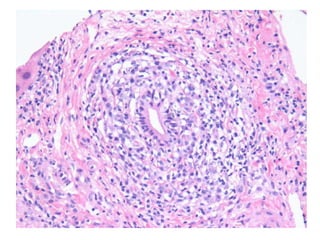

BS08-12291 36 yo, female.  Clinical history:  AMA 1:1280, rule out PBC.

BS08-12291 Dx: Primary biliary cirrhosis (diagnostic biopsy), Scheuer stage 2/4; cannot exclude overlap autoimmune hepatitis. Comment: Bile duct paucity and active, diagnostic duct destructive lesions are identified.  Some portal tracts are expanded by a prominent ductular reaction.  Significant scarring is not seen.  The degree of interface and lobular hepatitis is focally more severe than is typical for primary biliary cirrhosis and suggests the possibility of overlap autoimmune hepatitis; clinical correlation required.

BS08-12291 36 yo,female. Clinical history: AMA 1:1280, rule out PBC.

BS08-12291 Dx: Primarybiliary cirrhosis (diagnostic biopsy), Scheuer stage 2/4; cannot exclude overlap autoimmune hepatitis. Comment: Bile duct paucity and active, diagnostic duct destructive lesions are identified. Some portal tracts are expanded by a prominent ductular reaction. Significant scarring is not seen. The degree of interface and lobular hepatitis is focally more severe than is typical for primary biliary cirrhosis and suggests the possibility of overlap autoimmune hepatitis; clinical correlation required.